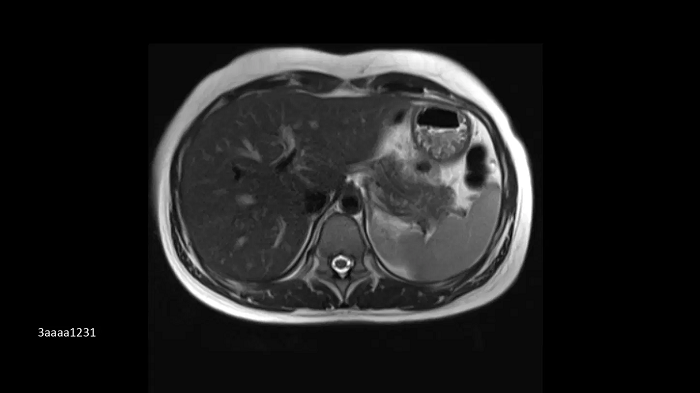

Compressed Sensing GRASP-VIBE

GRASP-VIBE Compressed Sensing for dynamic liver imaging in free-breathing patients who cannot hold their breath reliably.

- BioMatrix Spine 72

- Body 18

Image Credit: University Hospital Tübingen, Germany